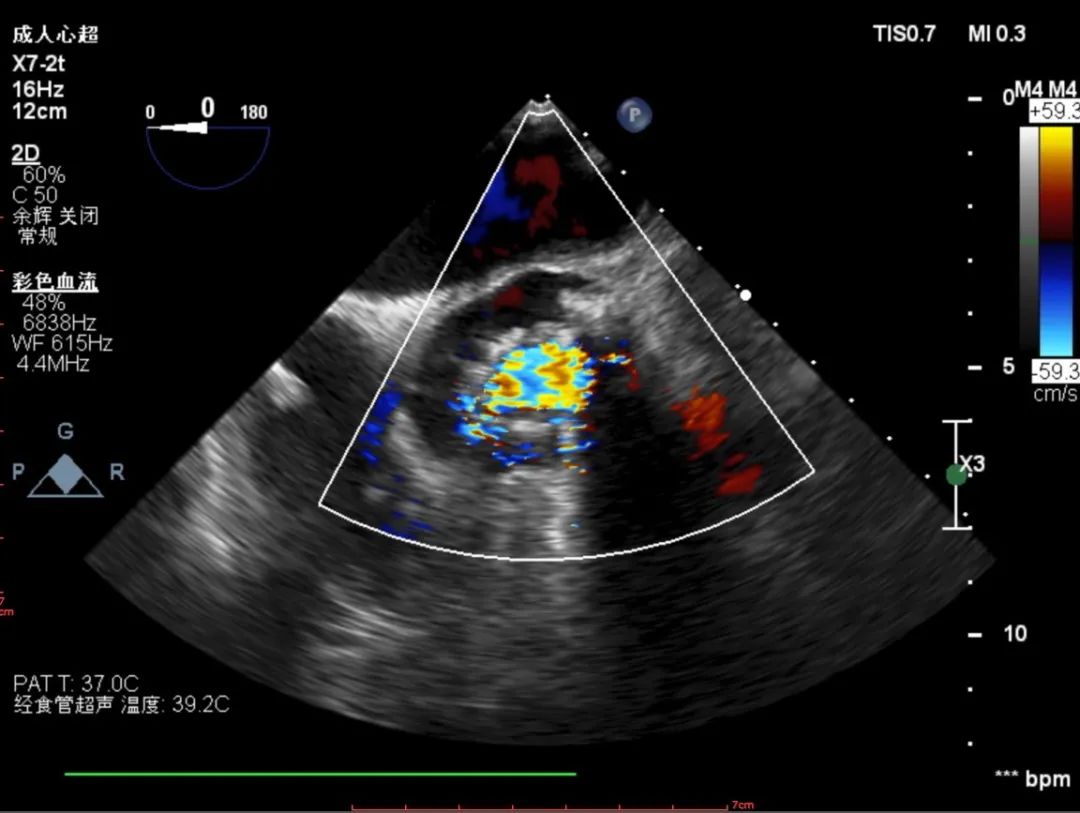

超声诊断:主动脉瓣叶为二叶式畸形,左右排列,瓣叶增厚,启闭不良,左房内径增大。诊断为主动脉瓣重度狭窄合并轻度关闭不全,Vmax =4.92m/s,PGmean =62mmHg,EF 54%。

彩超评估:

超声下观察瓣膜展开形态可,血流动力学改善明显

跨瓣压差:

术前跨瓣压差126mmHg,植入后跨瓣压差12mmHg